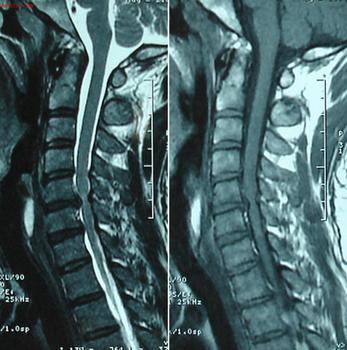

方法二、电子计算机断层扫描(CT):对于临床怀疑而X线不能确诊者,可以行CT检查。它能清晰显示骶髂关节间隙,便于测定关节间隙有无增宽,狭窄,强直或部分强直有独到之处。

方法三、磁共振(MRI)和单光子发射计算机断层扫描(SPECT):科学家研究了36例患者,24例为炎性下背痛,12例为机械压力所致下背痛的病人,通过标准的X线检查骶髂关节正常。但应用MRI检查:发现54%的炎性下背痛和17%的机械原因性下背痛的患者有骶髂关节炎。